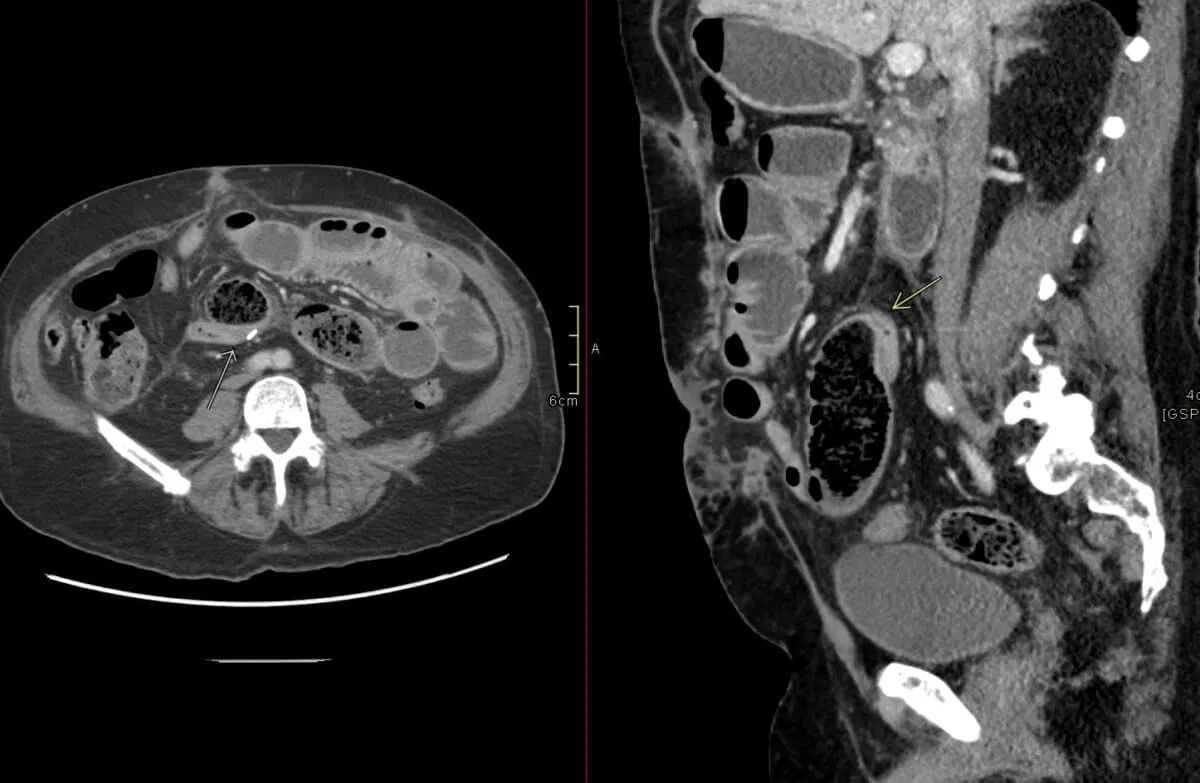

The small bowel feces sign is caused by stasis and dehydration of intestinal contents within dilated small bowel loops, most commonly due to chronic or subacute small bowel obstruction. This sign appears as particulate, fecal-like material mixed with gas bubbles on CT imaging, resembling colonic stool. It often localizes proximal to the transition zone of the obstruction, helping to identify the site and underlying pathology.

The term “small bowel feces sign” is used because the appearance of the intraluminal contentsโheterogeneous, particulate material mixed with gas bubblesโmimics the typical appearance of feces seen in the colon, despite its location in the small intestine. The designation highlights the radiological similarity to colonic stool, even though the material is actually partially digested food, desquamated epithelial cells, and mucus.

This sign develops due to prolonged stasis of enteric contents in dilated small bowel segments, usually caused by chronic or subacute obstruction. Slowed transit allows for progressive dehydration and concentration of luminal contents, leading to the formation of solid, particulate material that resembles feces. This is accompanied by increased absorption of water across the bowel wall, leaving undigested matter to accumulate.